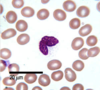

Sickle cells

Results in an abnormality in the haemoglobin found in RBCs. This leads to a rigid, sickle-like shape under certain circumstances. Also called “Drepanocyte”

Appearance: RBC damage, Hb globin chain malformation in humans, Sickle cell anaemia